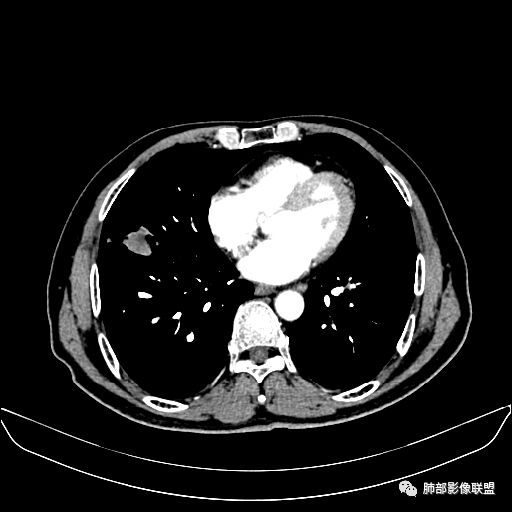

入院CT

老年男性,因“咳嗽咳痰1月余。”入院。病程中咳嗽咳痰,咳黄白痰,间断咯少许鲜红色痰血。PPD阳性。胸CT:右肺中叶外侧段支气管管腔阻塞,大片实性病变,病灶边缘光滑,部分边缘膨隆,可见分叶,肺门及纵隔可见肿大淋巴结,并可见钙化。增强可见病灶明显强化,而且延迟强化明显,病灶内多发低密度区,内见血管影,血管变细、部分血管破坏。考虑恶性病变可能性大,鉴别慢性肉芽肿性病变。

右肺中叶外侧段管腔阻塞、实性病变,病灶边缘光滑,可见分叶,肺门及纵隔可见肿大淋巴结,并可见钙化。增强可见病灶内多发低密度区。

老年男性,咳嗽、咳痰1月余,间断血痰。PPD阳性。

胸CT:跨叶大肿块,主体在中叶,右中叶外侧段支气管阻塞,病灶部分边缘膨隆,可见分叶,部分边缘平直,肺门及纵隔可见肿大淋巴结。增强病灶不均匀强化,延迟强化明显,病灶内多发低密度区,内见血管飘浮,部分血管变细、模糊。考虑:恶性病变可能性大,大细胞?淋巴瘤?鉴别慢性肉芽肿性病变。

右肺中叶软组织肿块,外围向内生长,叶间胸膜向前内移位,肿块近肺门侧跨叶,中叶外侧段支气管截断,密度不均匀,双侧肺门及隆突下见肿大淋巴结,增强后呈中度不均质强化,肺动脉供血,多发坏死区,边界尚清,坏死区域内见结构,结合病史考虑恶性,鉴别诊断1结核,爬行征是沿支气管树分布,外宽,内窄,周围有卫星灶,内气管狭窄后扩张,此例沿叶间胸膜长轴分布,气管有截断,不典型。2炎性肉芽肿,符合的地方下方层面增强后延迟性轻度环形强化,不符临床无发热等急性感染病史,实验室指标不符,病灶周围渗出及慢性炎性改变有,不明显。